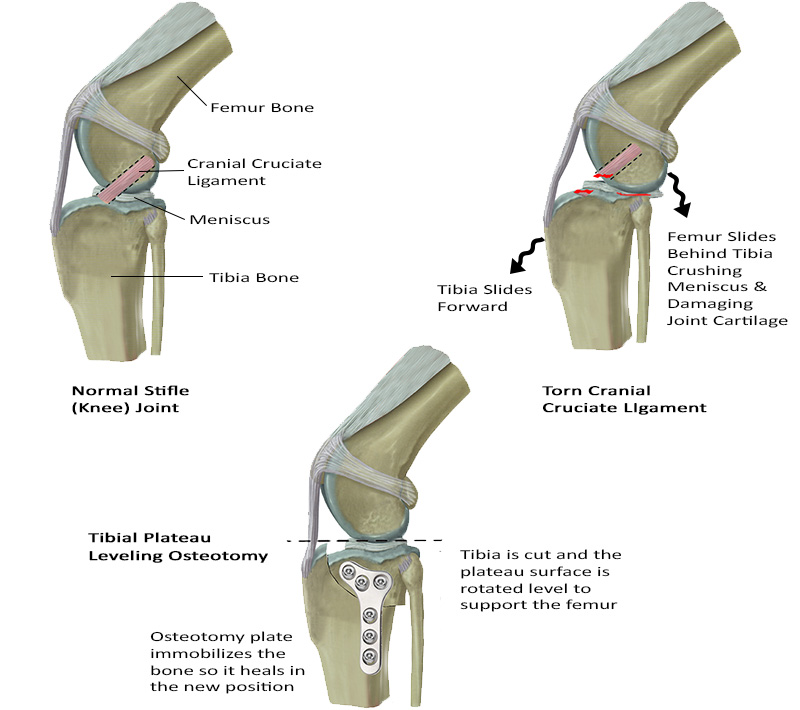

The illustration below shows the anatomy of a normal dog knee joint with an intact and a torn cranial cruciate ligament. The cranial cruciate ligament normally keeps the femur bone in position on top of the tibia, with the meniscus (a cartilage pad) acting as a cushion between the bones.

When the CCL is torn in dogs the tibia falls forward (called tibial thrust) and the femur slides down the back of the tibia. This abnormal movement is called a “positive cranial drawer sign” and can be identified by a veterinarian when examining the leg. With each step the femur slides back crushing the meniscus and scraping the joint surface causing pain and damage to the joint. If the joint is not stabilized it will develop painful arthritis and permanently limit the dog’s mobility and enjoyment of normal activities.

Tibial Plateau Leveling Osteotomy (TPLO) surgery levels the top of the tibia, called the “Tibial Plateua”, and creates a stable surface for the femur to rest upon. This stabilizes the femur and eliminates the abnormal sliding action that is causing damage to the joint.

To accomplish leveling of the tibia, the top of the tibia is cut and rotated to realign it under the femur. A metal plate is placed to hold the bone in position while it heals into this new alignment.

The change in biomechanics of the joint after TPLO eliminates the need for a cranial cruciate ligament so it will be trimmed or removed during surgery. The meniscus will also be examined and any damaged areas will be removed to reduce pain and inflammation.

The illustrations below demonstrate how the TPLO surgery works: